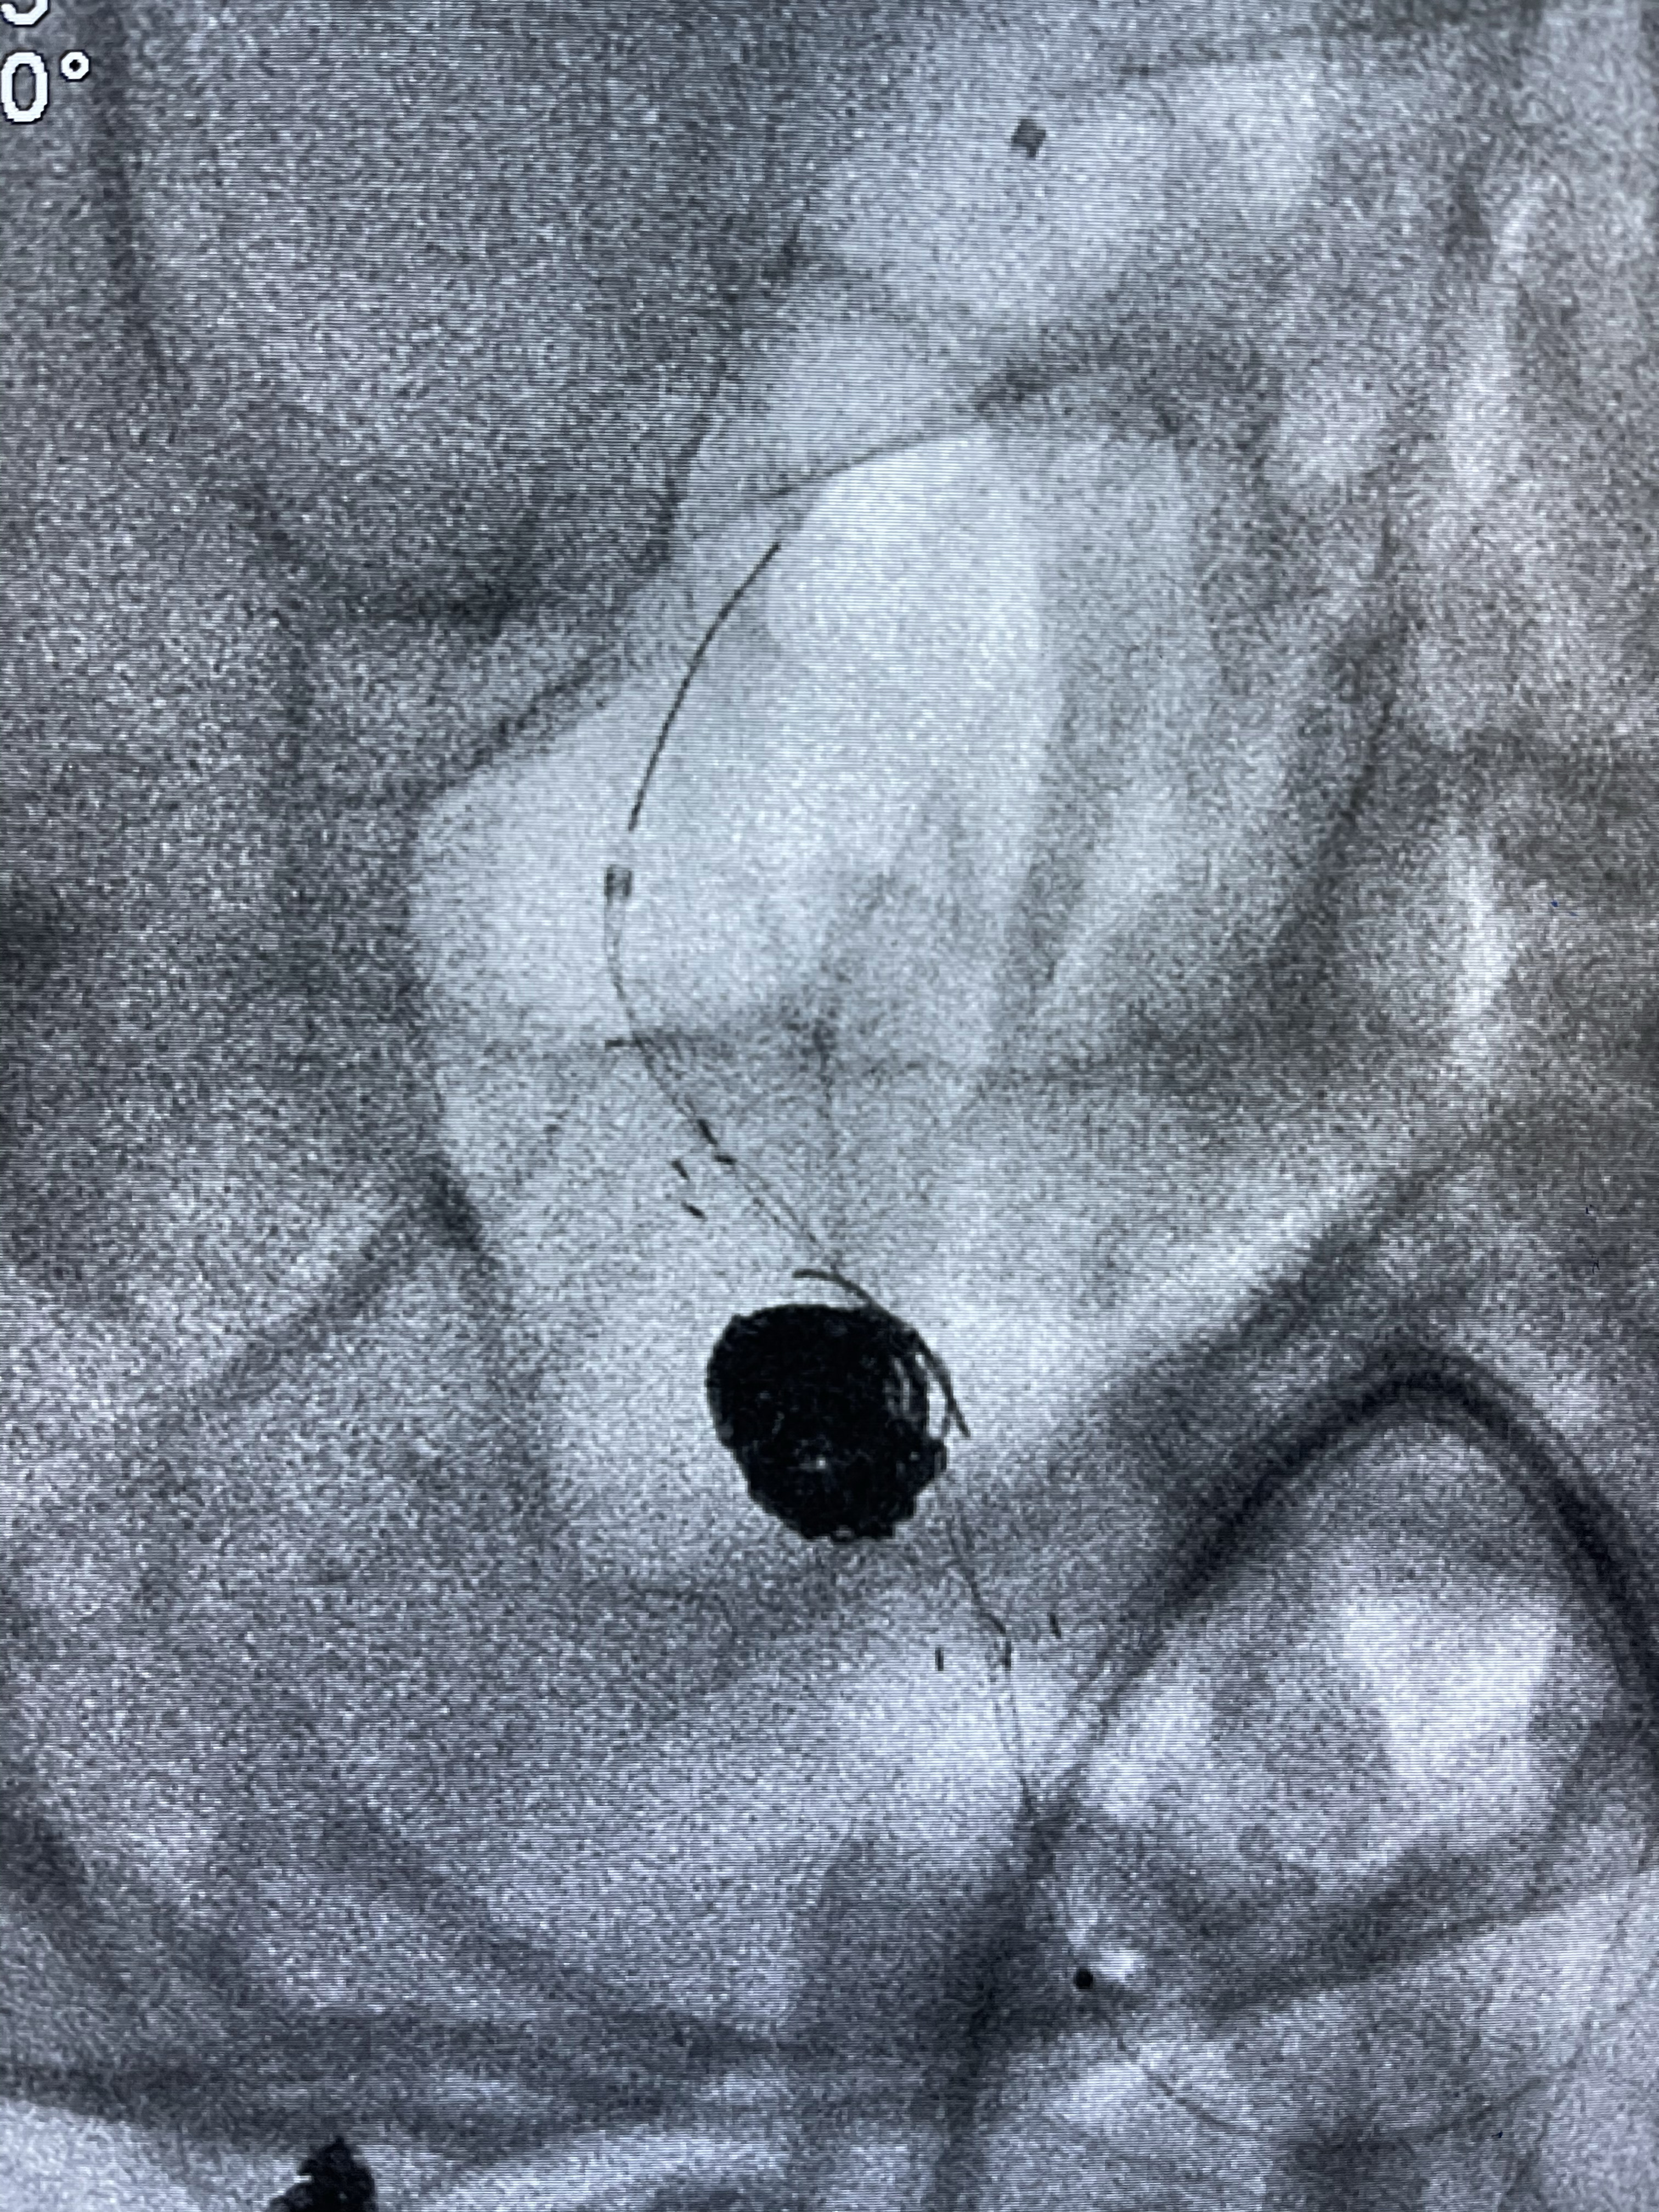

支架到位

支架释放,透视下